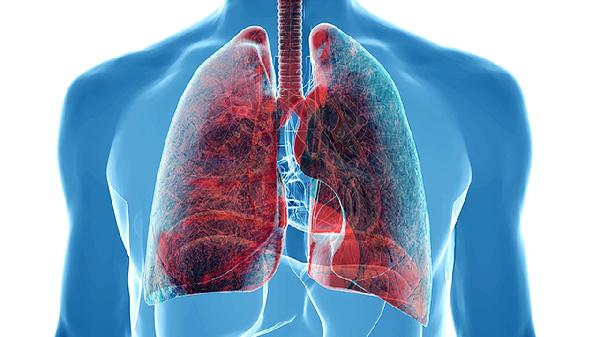

雾霾中的细颗粒物和有害气体被吸入人体后,可能沉积在呼吸道和肺泡中,导致局部刺激和炎症反应。长期暴露于高浓度雾霾环境中,可能引发慢性支气管炎或肺功能下降。减少外出、佩戴防护口罩有助于降低污染物吸入量。

雾霾中的二氧化硫、氮氧化物等刺激性气体可直接损伤呼吸道黏膜,引发炎症反应。炎症可能导致气道高反应性,表现为喘息、气促等症状。使用布地奈德吸入气雾剂、孟鲁司特钠片、盐酸氨溴索口服溶液等药物可缓解症状。

雾霾中的超细颗粒物可进入血液循环,引起血管内皮功能障碍和氧化应激反应。这些变化可能增加心肌缺血、心律失常等心血管事件的发生概率。控制基础疾病、避免剧烈户外活动是重要的预防措施。